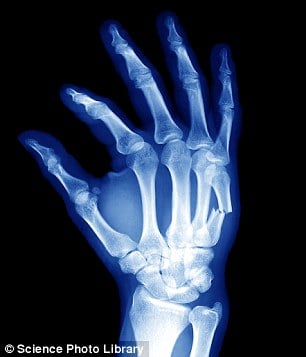

-The human hand, including the wrist, contains 54 bones.

-Gliding joints are found between flat bones that are held together by ligaments. Some bones in the wrists and ankles move by gliding against each other.